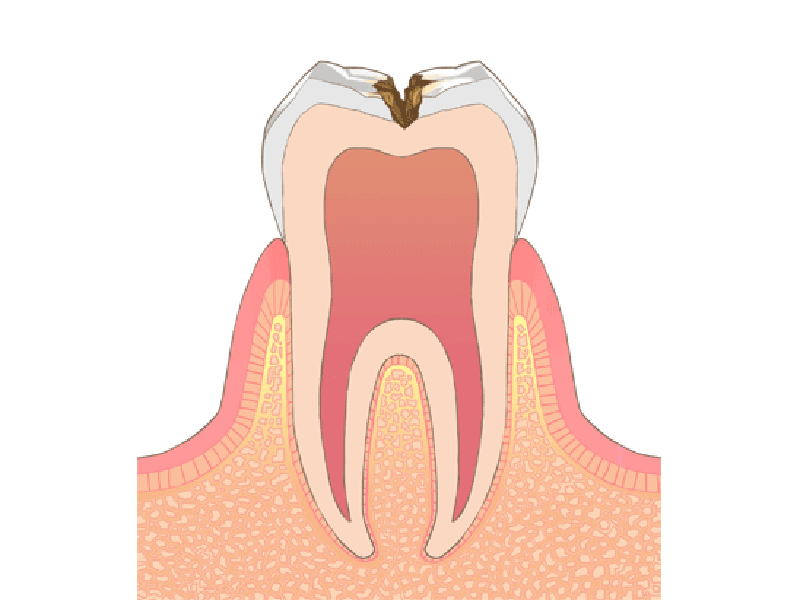

神経の近くまでむし歯が進行した場合

この様な場合は、むし歯が中期まで進行している可能性があります。

神経までむし歯が達した場合

むし歯が後期まで進行している可能性があります。 当院ではなるべく歯を残すことができるようマイクロスコープを使った根管治療を行っています。

なるべく歯を残す精密根管治療

根管とは歯の神経が入っている非常に細い管です。むし歯で神経を除去した後は根管内に侵入した細菌を除去する必要があり、これを根管治療と呼びます。根管治療がしっかりできていないと根管内で菌が繁殖して再治療することになりますから、非常に重要な治療です。

根管は細いうえに曲がりくねっていることもあるので、肉眼で内部を見ることはできません。そのため、当院ではマイクロスコープを使用して精度が高い「精密根管治療」を行っています。